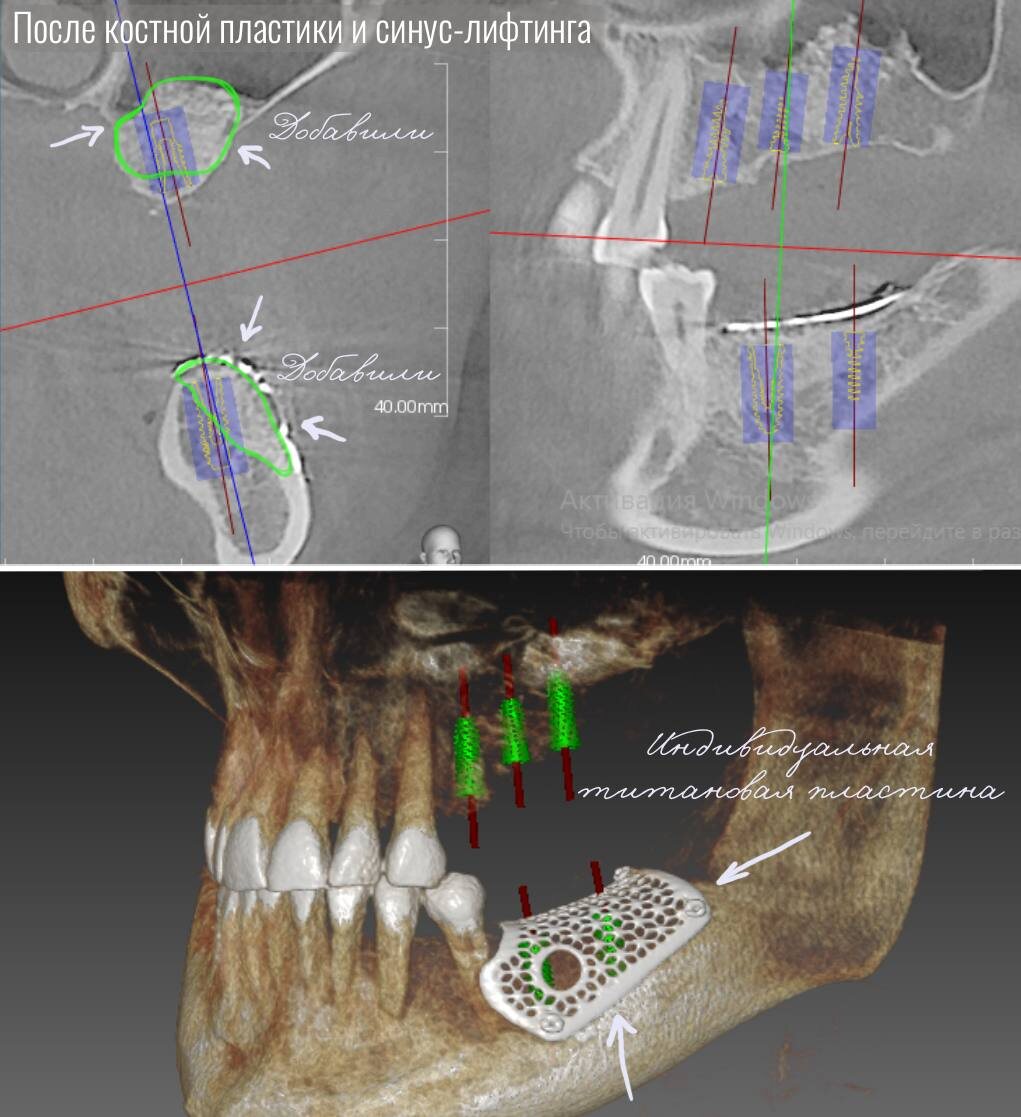

Мы не хотели допускать дополнительную травматизацию и еще больше увеличивать сроки реабилитации, поэтому было принято решение использовать индивидуальную титановую пластину, смоделированную по компьютерной томографии пациента.

Пластина создаёт прочный каркас, под который помещается искусственный костный материал в виде гранул, смешанный с собственной кровью пациента. Со временем в этой области формируется новая кость — этот метод называется направленная костная регенерация (НКР).

1. В зону дефекта костной ткани помещают костнозамещающий материал и закрывают его титановой пластиной.

2. Пластина блокирует быстрорастущие мягкие ткани от проникновения в область дефекта. Это позволяет более медленно растущим костным клеткам заселить пространство и сформировать новую кость.

Индивидуальные — изготавливаются заранее по 3D-снимку пациента. Пластина полностью повторяет форму дефекта и нужного будущего объема кости.

В случае нашего пациента именно индивидуальная пластина стала оптимальным и наиболее безопасным решением.